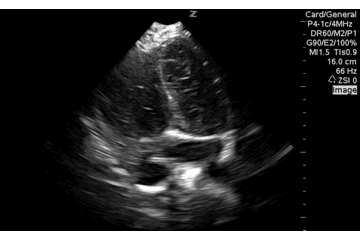

When you see both ventricles pretty well but not he atrium you are foreshortened in the aprical four chamber echocardiography view. Flatten the probe (proximal probe closer to the chest wall) and open up all four chambers.